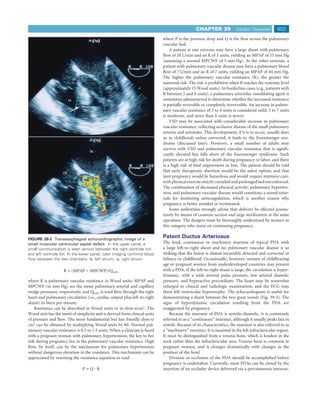

ASD can be difficult to diagnose during pregnancy. The murmur                                                  RA

lung fields. Echocardiography establishes or confirms the diagnosis                                                LA

(Fig. 39-1), obviating the need for cardiac catheterization in many

cases.

fibrillation, right ventricular dysfunction, and pulmonary hyperten-          FIGURE 39-1 Transesophageal echocardiographic image of atrial

sion rises significantly. Pregnancy is not advised if any of these sequelae   septal defect (ostium secundum). In the upper panel, a large defect

is present. If the patient insists on going through with the pregnancy,      in the interatrial septum is present. In the lower panel, the blue/

prolonged bed rest will be required, and vigorous treatment of heart         yellow color represents blood flow from the left atrium (LA) into the

failure may be needed. The maternal risk is increased, and there is sig-     right atrium (RA). RV, right ventricle.